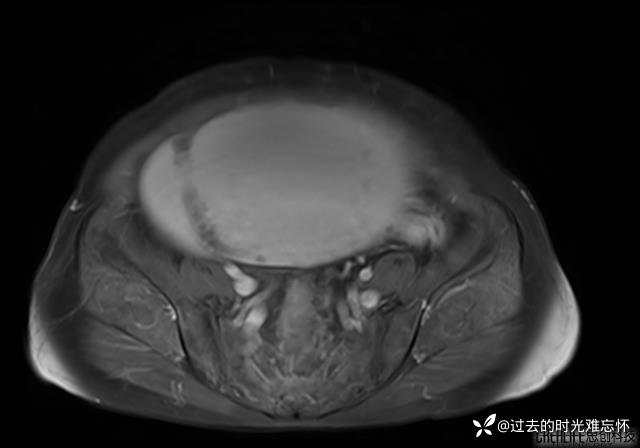

患者性别:女

患者年龄:65岁

主诉: 发现腹部隆起半年余。无其他明显不适。

浆液性囊腺瘤 (22)